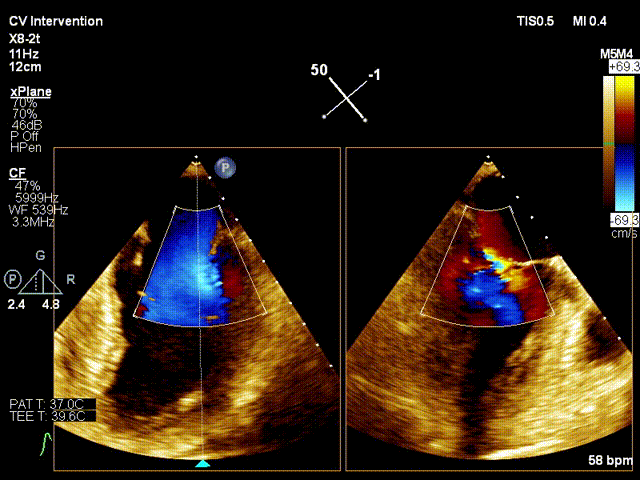

行TEE示:二尖瓣前叶A3脱垂合并重度反流(DMR4+),脱垂宽度11.6mm,脱垂高度5.8mm、二尖瓣口舒张期几何面积 6.00cm²、收缩期二尖瓣口偏心性反流束缩流颈宽度8.0mm、PISA定量瓣口EROA=0.61cm²。

患者平卧导管床,常规消毒铺巾,呼吸机辅助呼吸,穿刺右侧股静脉,于经食道超声指导下穿刺房间隔,造影确认穿刺针位于左房后。予super stiff置入左上肺静脉。于右股静脉沿super stiff推送MitraClip Guide Catheter于左房。于经食道超声指引下,推送XTR Clip Delivery System至二尖瓣左房面,食道超声确认12点钟方向推送至二尖瓣左室面,重新调整DC handle使Clip Arm至11点钟方向。顺利捕捉二尖瓣前叶A3及后叶P3区域,Grap down后夹闭Clip Arm。经食道超声评估二尖瓣返流由MR4+减少至微量,确认前叶有效夹持长度13mm,后叶有效夹持长度为11mm,确认瓣叶夹持牢固,释放瓣膜夹。经食道超声再次评估二尖瓣返流微量,二尖瓣压差1mmHg,退出MirtaClip系统,3DTEE评估房间隔 穿刺口少量左向右分流,未见右向左分流,未见心包积液,结束手术。

行TEE示:房间隔卵圆窝膨胀瘤改变;房间隔穿刺高度37mm;二尖瓣前叶 长度20.9mm,后叶长度10.9mm;二尖瓣面积4.94cm2;左冠状动脉内径增宽;收缩期 二尖瓣口偏心性反流束缩流颈宽度6.2mm,反流束起源于A1/P1及前交界,PISA定量反 流EROA=0.51cm2,舒张期二尖瓣口平均跨瓣压差1mmHg。

患者平卧导管床,常规消毒铺巾,呼吸机辅助呼吸,穿刺右侧股静脉,于经食道超声指导下穿刺房间隔,确认穿刺针位于左房后交换房间隔穿刺导管至左房, 再予super stiff置入左上肺静脉;退出房间隔导管后予16F预扩张鞘扩张右股静脉;于右股静脉沿Super stiff推送24F MitraClip steerable Guide Catheter于左房, 于3DTEE指导下,推送NTR Clip Delivery System至二尖瓣左房面,3DTEE确认12点钟 方向推送至二尖瓣左室面,重新调整DC handle使Clip Arm至11点钟方向。顺利捕捉 二尖瓣前叶A1及后叶P1区域,Gripper down后夹闭Clip Arm,3DTEE评估二尖瓣反流 由MR4+减少至1+,确认A1有效夹持长度8mm,P1有效夹持长度8mm,确认瓣叶夹持牢固, 释放瓣膜夹,3DTEE再次评估二尖瓣反流1+;退出MitraClip系统,3DTEE评估房间隔 穿刺口少量左向右分流,3DTEE评估房间隔 穿刺口少量左向右分流,未见右向左分流,未见心包积液,结束手术。